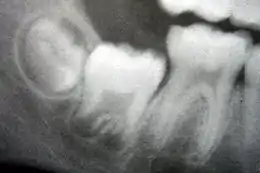

La dentition primaire commence à l'arrivée des incisives centrales de la mandibule, habituellement à huit mois, et dure jusqu'à ce que les premières molaires permanentes apparaissent dans la bouche, généralement avant six ans[26]. Les dents primaires sortent dans l'ordre suivant : (1). incisive centrale, (2) incisive latérale, (3) la première molaire, (4) canine et (5) deuxième molaire[27]. En règle générale, il y a quatre éruptions de dents tous les six mois ; les dents mandibulaires sortent avant les dents maxillaires et l'éruption des dents se produit plus tôt chez les filles que les garçons[28]. Au cours de la dentition primaire, les bourgeons dentaires des dents permanentes se développent sous les dents primaires, sur le versant lingual ou palatin.

La dentition mixte commence lorsque la première molaire permanente apparaît dans la bouche, généralement à six ans, et dure jusqu'à ce que la dernière dent de lait soit perdue, le plus souvent à onze ou douze ans[29]. Les dents permanentes du maxillaire sortent dans un ordre différent des dents permanentes de la mandibule. Les dents du maxillaire sortent dans l'ordre suivant : (1) première molaire (2) incisive centrale, (3) incisive latérale, (4) première prémolaire, (5) deuxième prémolaire, (6) canine, (7) deuxième molaire et (8) troisième molaire. Les dents de la mandibule sortent dans l'ordre suivant : (1) première molaire (2) incisive centrale, (3) incisive latérale, (4) canine, (5) première prémolaire, (6) deuxième prémolaire, (7) deuxième molaire, et (8) troisième molaire. Comme il n'y a pas de prémolaires dans la dentition primaire, les molaires primaires sont remplacées par les prémolaires permanentes[30]. Si les dents primaires sont perdues avant que les dents permanentes ne soient prêtes à les remplacer, les dents postérieures peuvent se déplacer vers l'avant et réduire l'espace disponible pour la future dent[31]. Cela peut provoquer des chevauchements et/ou des malpositions des dents permanentes, ce qu'on appelle généralement « malocclusion ». Une orthodontie peut être alors nécessaire dans de telles circonstances pour réaligner les dents.